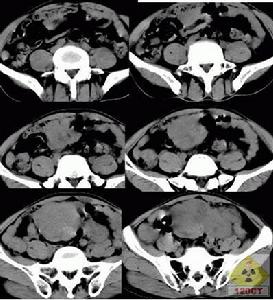

精原細胞瘤多發生於中年以後,常為單側性,右側略多於左側。發生於隱睪的機率較正常位睪丸高几十倍。本瘤為低度惡性。85%的患者睪丸明顯腫大,腫瘤局部侵犯力較低,腫瘤一般有明顯界限。精原細胞瘤發展較慢,一般先轉移至腹膜後淋巴結,後期也可發生廣泛血道播散,確診時,臨床期病例占60%~80%。

精原細胞瘤的病理類型與預後有關,腫瘤擴散的程度和轉移的範圍也影響著預後。故臨床醫生不僅要了解腫瘤的病理類型,而且要根據病變範圍的不同來制定相應的治療方案。因此確定每個患者病變分期是有實際意義的。當今最常採用的分期方法為:

Ⅰ期:腫瘤只局限於睪丸及附睪內,而尚未突破包膜或侵入精索,無淋巴結轉移。

Ⅱ期:由體格檢查、X線檢查證實已有轉移,可擴散到精索、陰囊、髂腹股溝淋巴結,但未超出腹膜後淋巴區域。轉移淋巴結臨床未能捫及者為Ⅱa期,臨床檢查捫及腹腔淋巴結者為Ⅱb期。

Ⅲ期:已有橫膈以上淋巴結轉移或遠處轉移。也有研究者把遠處轉移者歸入Ⅳ期。

任何睪丸腫瘤應先行高位睪丸摘除術,然後根據病理類型和臨床分期選擇治療方案。精原細胞高度放射敏感,較低劑量就能消滅轉移病灶而不產生明顯的放射損傷,臨床Ⅰ期睪丸精原細胞瘤,睪丸高位摘除後,應對同側髂淋巴結和腹膜後淋巴結進行預防性照射,直線加速器高能射線、60Co和千伏X線均可作為外照射源。但不必進行高劑量預防照射。

臨床Ⅱ期睪丸精原細胞瘤的治療

臨床Ⅱa期,腹膜後轉移淋巴結較小,照射野同臨床Ⅰ期;臨床Ⅱb期轉移淋巴結較大,應根據轉移灶大小設計照射野至充分包括淋巴結,腹腔廣泛轉移者,應進行全腹照射。臨床Ⅱ期放射治療劑量分割同臨床Ⅰ期,照射中平面劑量25Gy後,Ⅱa期縮野增強照射轉移淋巴結10Gy,中平面總劑量應達到35Gy/4~5周以上;Ⅱb期增強照射15Gy,總劑量達到40Gy。臨床Ⅱ期睪丸精原細胞瘤,是否需要進行縱隔和左鎖骨上區預防放射,仍有爭議。

臨床Ⅲ期和Ⅳ期睪丸精原細胞瘤的治療

臨床Ⅱ期、Ⅲ期和Ⅳ期睪丸精原細胞瘤均需進行放射與化療的綜合治療,Ⅲ期病例治療方法同Ⅱ期,但縱隔及左鎖骨上區轉移淋巴結的照射劑量應達到35~40Gy/5~6周。臨床Ⅳ期病例治療前已有遠處轉移,應以化療為主,輔以放療控制局部病灶,不作預防性放射。治療以套用化療放療-化療,即“三明治”技術為合理,即先作3個療程化療,爾後照射35~40Gy/5~6周,再進行3~4個療程化療。